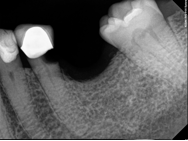

Conventional endodontic treatment with alloy core build up

Conventional Endodontic Treatment with Post and Core Coronal Restoration